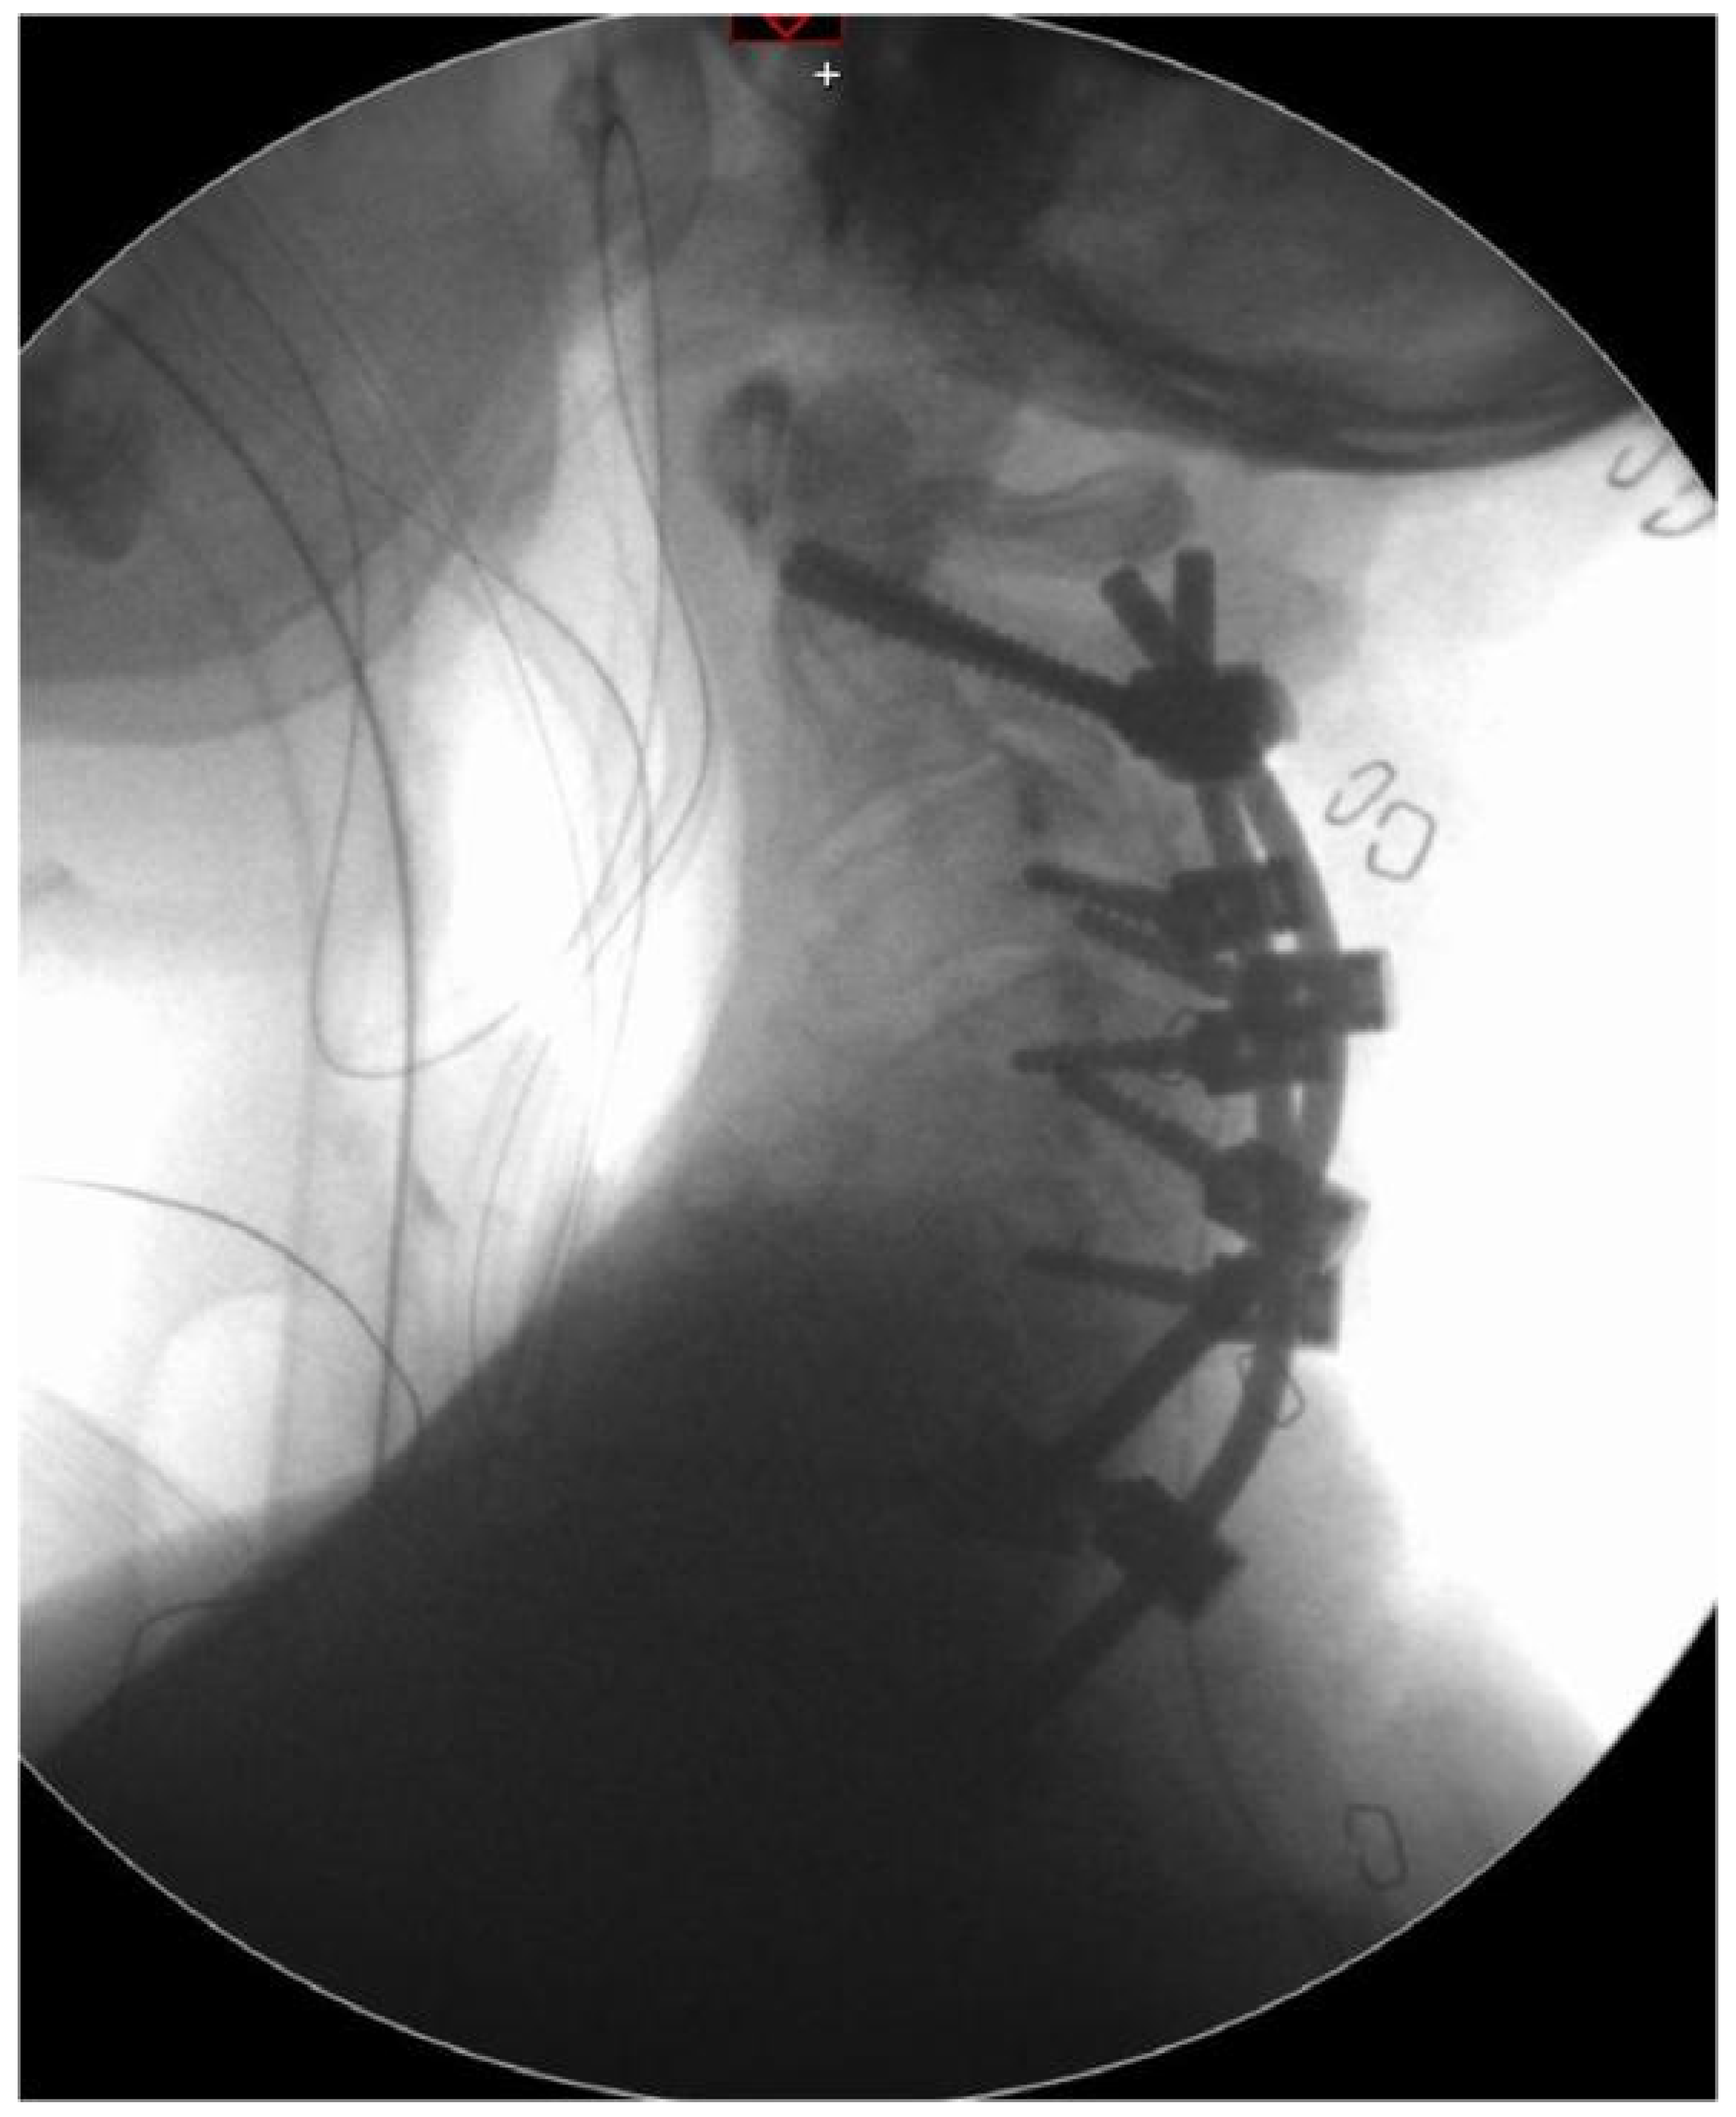

4. Surgical Procedure

5. Follow-Up Control